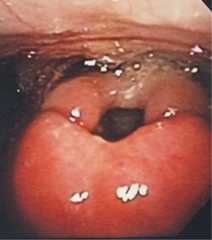

Figure 2.

Laryngoscopy image of epiglottis showing erythematous and enlarged epiglottis.